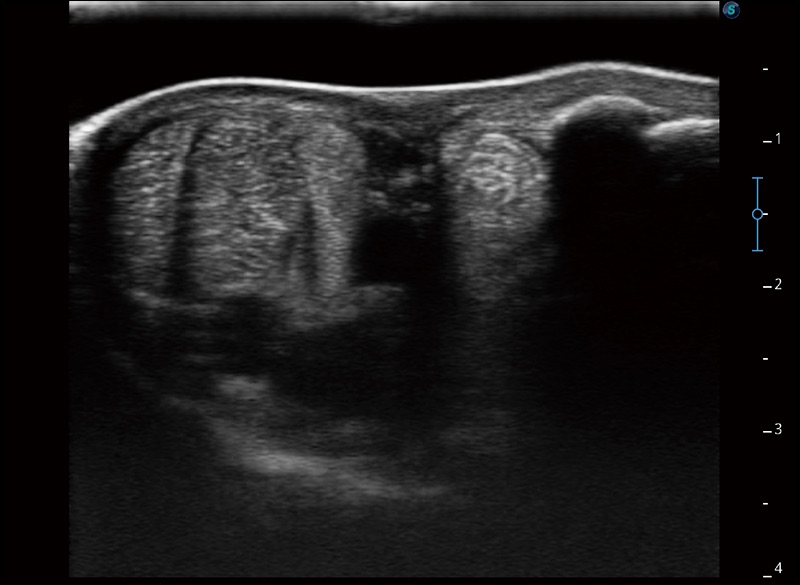

α1卓越的图像质量和便捷的工作流程,使每位宠物医生都能轻松扫查。其全面的兽用应用功能和紧凑型的结构设计,可以满足动物检查的多种需要。专业的预设检查模式和多领域测量软件包有助于为不同类型的动物提供检查, 让宠物医生能够出色的完成工作。

实时宽景成像

可实时观察感兴趣区域和病变位置